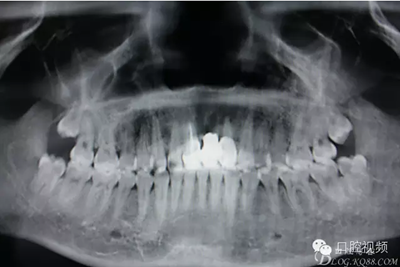

【原創(chuàng)博客】烤瓷橋下的悲劇-張東星